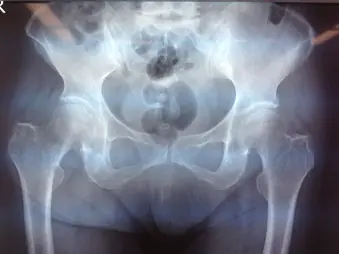

疼痛が持続するため、3週間後に再受診。レントゲン、CTにて右大腿骨頸部骨折を認め、手術目的に入院となった。

GardenⅡ型、PauwelsⅢ型の骨折を認める